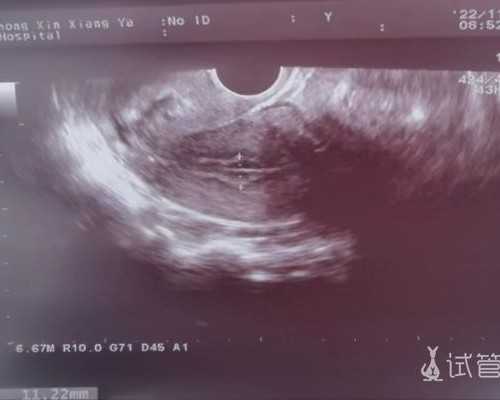

试管婴儿的治疗开始于月经第2天或第3天的卵巢刺激,持续约10-12天,随后大约2-3天后收获卵子并转移胚胎。